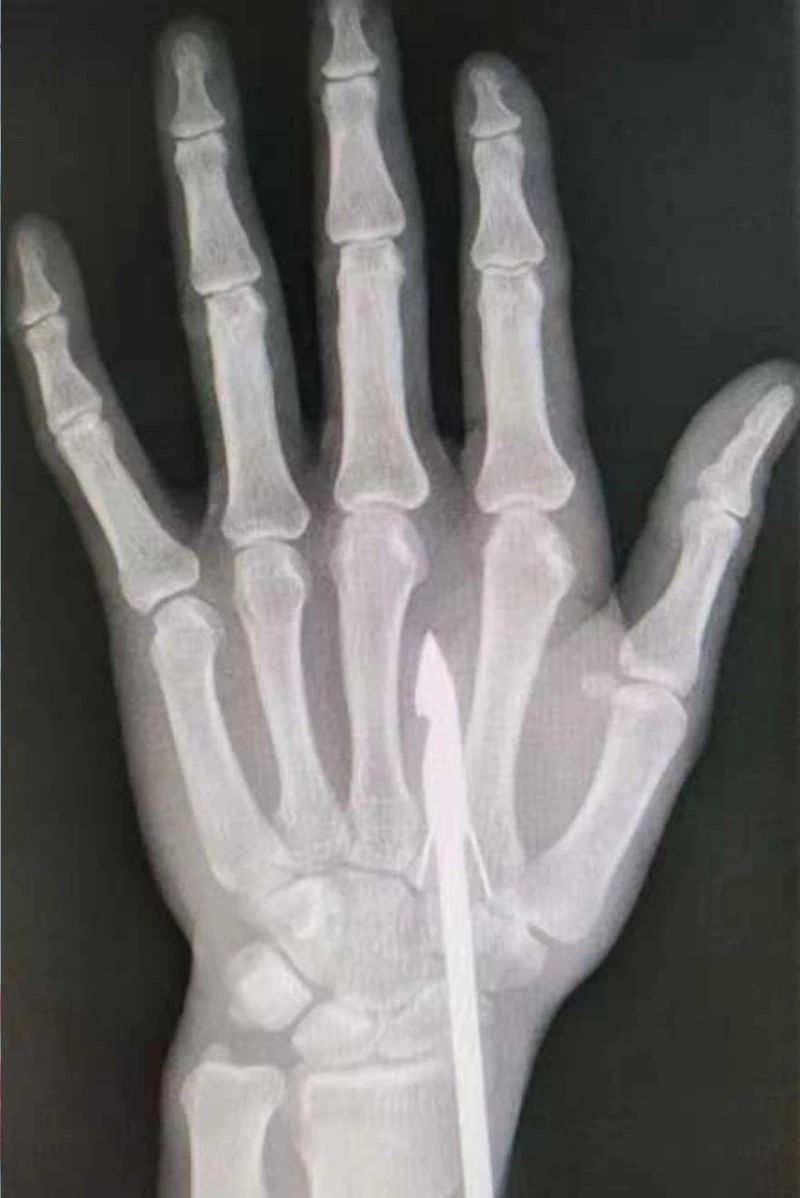

時(shí)間緊迫,每一秒的流逝都可能對(duì)傷者的手部功能造成不可逆的損害。接診醫(yī)生代彭威,迅速對(duì)傷者進(jìn)行了初步檢查。他注意到,魚鉤已經(jīng)深深嵌入皮膚,情況遠(yuǎn)比表面看起來復(fù)雜。沒有絲毫猶豫,立即安排了X線檢查以確認(rèn)魚鉤的位置及傷及范圍,以及急診化驗(yàn)檢查以評(píng)估患者的整體狀況。

確保在取出魚鉤的同時(shí),不對(duì)周圍的組織造成額外的傷害。8點(diǎn)15分左右患者在局部浸潤(rùn)麻下進(jìn)行手術(shù),經(jīng)探查后魚鉤未傷及重要血管、神經(jīng)及肌腱,經(jīng)過緊張的十分鐘,魚鉤終于被順利取出,隨后對(duì)傷口進(jìn)行了仔細(xì)的清理和縫合,用敷料仔細(xì)包扎,確保傷口能夠順利愈合。